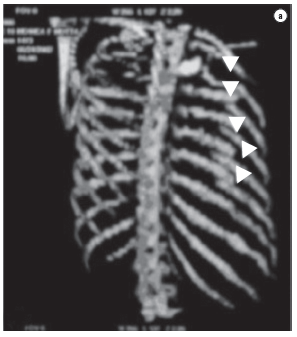

A 32-year-old female patient suffered an automobile accident which resulted in left hemopneumothorax, left pulmonary contusion and double fractures extending from the third to the eighth left costal arches, as seen on chest X-rays and computed tomography scans of the chest (Figures 1 and 2). Tomography of the skull, cervical spine, abdomen, and pelvis, were normal, as were the electrocardiogram and echocardiogram, as well as the results of tests for muscle enzymes and markers of myocardial necrosis. Water-sealed thoracic drainage was performed, and the implantation of an epidural catheter was inserted in order to provide continuous analgesia using an infusion pump. The patient presented significant chest deformation and pain, despite high doses of painkillers. It was expected that this profile, unless surgically treated, would evolve to complex deformation of the chest wall, with possible respiratory impairment. The patient did not require mechanical ventilation. In view of this clinical profile, surgical treatment was indicated in order to stabilize the fractures. The procedure was performed using left posterior lateral thoracotomy. We found double fractures extending from the third to the eighth left costal arches, with complete rupture of various intercostal pedicles, herniation, and impaction of the fractured segment (six arches) within the pleural cavity, with significant compression of the pulmonary parenchyma (traumatic thoracoplasty). We performed reduction of the fractures and fixation of the ribs with number 5 steel wires, perforating the extremities of the ribs with a nº 2 drill, passing the steel wire from one rib segment to another, and tying it. A chest tube was inserted and left in place until the third day. The patient evolved to excellent pain control and improved respiratory dynamics. Postoperative X-rays and tomography scans confirmed the favorable result of the surgical treatment (Figure 3).

Closed chest trauma is an important cause of morbidity and mortality, principally when accompanied by flail chest. It occurs when there are multiple fractures of the chest cavity, more specifically when we observe fractures of three or more ribs, at two or more points, together with fluctuation, paradoxical breathing, or both.(3) Traumatic thoracoplasty can be defined as a condition in which the fractured segment migrates into the chest and becomes lodged within the segments of the fixed costal arches, causing impaction of this segment within the pleural cavity. This causes intractable pain (permanent traction of intercostal nerves) and compresses the pulmonary parenchyma, considerably worsening the clinical profile of the patient. Severe flail chest is associated with respiratory failure, due to the retention of secretions, atelectasis, pneumonia, and, later, restricted mobility of the chest cavity.(2) Thoracic instability can be efficiently treated with analgesia, preferably epidural, and physical therapy, with proper secretion mobilization.